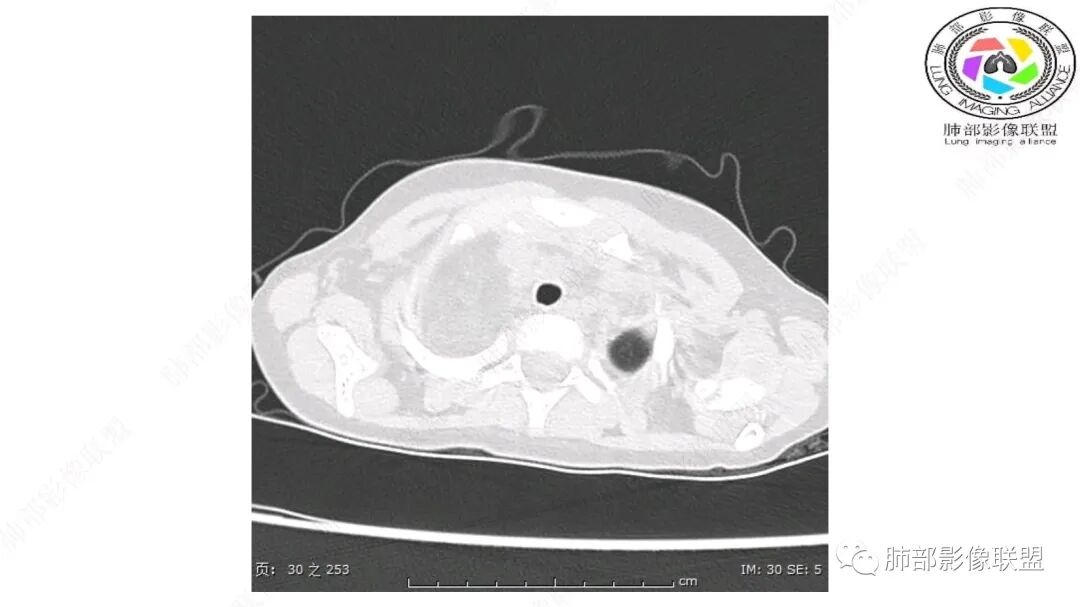

患儿3岁 咳嗽检查发现纵隔占位。右肺上叶受压表现,占位以脂肪组织密度为主,似见分隔,首先考虑为脂肪母细胞瘤,鉴别脂肪瘤,畸胎瘤。

幼儿,右上纵隔团块状脂肪密度影,边缘清晰,内可见血管及支气管穿行,考虑脂肪瘤,鉴别畸胎瘤。

幼儿,右上纵膈团块,脂肪密度,内见分隔,增强病灶内见血管穿行,结合患者年龄,考虑脂肪母细胞瘤,鉴别脂肪瘤。

CT扫描对脂肪类肿瘤常有独到价值。肿块孤立、边界清楚,未见周围浸润,较均匀脂肪样低密度,高度提示为良性!

发生于成人为脂肪瘤表现,婴幼儿自然会想到脂肪母细胞瘤。两者生物学行为并无本质区别。

脂肪母细胞瘤由成熟程度不同的脂肪组织、纤维间隔、黏液基质、小血管丛等间质成分组成,以脂肪组织与黏液样基质为主,其影像学表现取决于上述组织成分。典型的CT和MRI表现为:前后纵隔均可发生,常见于前纵隔;肿块大小不一,直径多在3cm~7cm,密度均匀,CT值呈水样或脂肪密度,脂肪组织密度或信号为主的肿块,其内密度或信号不均匀,可见粗细不一的分隔影,且有结节、片状影,后者可呈轻中度强化;结节状肿瘤包膜完整;弥漫性者包膜不明显,常呈浸润性生长;周围结构为受压和推移改变,可有少量胸腔积液,淋巴结无增大。